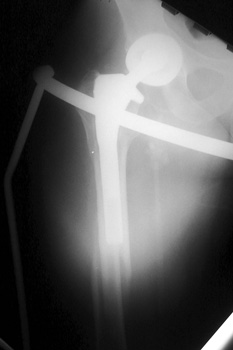

Insufficiency fracture lateral tibial plateau in patient with long revised left femoral stem

STRESS REACTION

Stress reaction secondary to altered biomechanics. Cortical thickening is present medial to the femoral component tip.